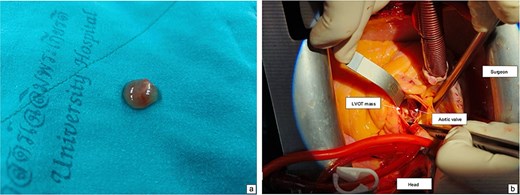

Intraoperative view showing mass attached to the left ventricular outflow tract (a). A gross specimen of the excised mass (b).

The patient underwent surgical excision of the LVOT mass via a median sternotomy. Cardiopulmonary bypass (CBP) was established using arterial cannulation in the ascending aorta and single, two-stage venous cannulation via the right atrium. An oblique aortotomy was performed to access the LVOT, and the mass was completely excised. The aorta was closed with 4–0 Prolene, and the excision site was inspected to ensure no residual tissue. Hemostasis was achieved, and CBP was weaned off once adequate cardiac function was confirmed. Two tube drainages in pericardial and mediastinal spaces. The pericardium was closed, with a total CBP time of 45 min, an aortic cross-clamp time of 27 min, and a total operative time of 3 h and 12 min. Gross pathology showed a 1 × 1 × 0.3 cm irregular, soft, grey-white polypoid mass. Histology examination of the mass revealed multiple branching papillary fronds with a central avascular collagen, lined by a layer of hyperplastic epithelial cells, consistent with papillary fibroelastoma (Figs 3 and 4).